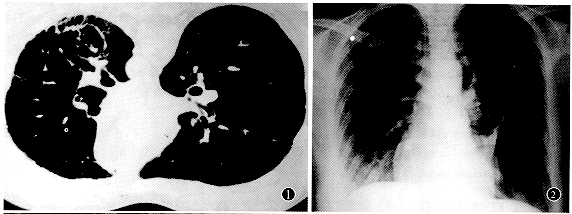

患者女性, 27岁,1989年突发右侧胸痛伴呼吸困难,胸片示:右侧气胸,经抽气治疗后好转。1993年9月因左侧气胸入院,给予抽气治疗,同时作胸部CT示:双肺弥漫性薄壁囊状影 ......